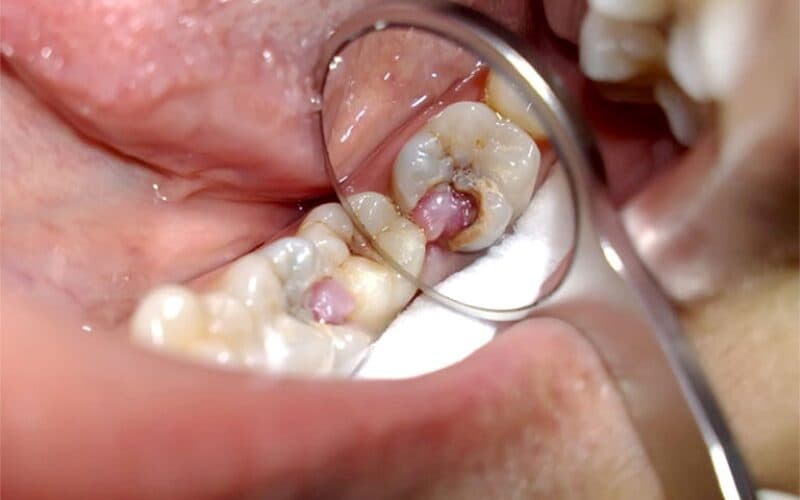

Trẻ em bi sâu răng hàm bắt nguồn từ nhiều nguyên nhân

Số lượng trẻ bị sâu răng hàm ngày càng tăng chủ yếu do vị trí của răng. Răng hàm nằm ở khu vực dễ bị sâu – vị trí phía trong sâu khoang miệng. Những rãnh của răng hàm chính là vị trí thuận lợi để cho thức ăn mắc vào. Lâu ngày, chúng sẽ phát triển thành vi khuẩn và gây sâu răng.

Bên cạnh đó, răng hàm có nhiệm vụ chính trong việc nhai, nghiền thức ăn. Do đó, men răng hàm sẽ dễ bị bào mòn và yếu đi theo thời gian.